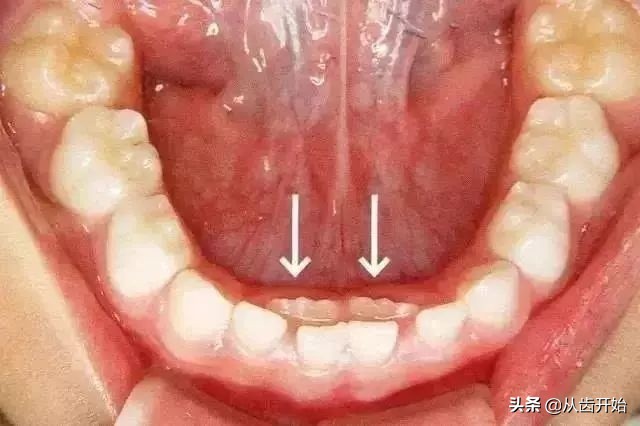

乳牙滞留

如果孩子的恒牙已经萌出,乳牙却“不肯”脱落,就叫做乳牙滞留。

主要原因:★ 恒牙胚错位 ★ 过于精细化食物减少了摩擦力导致萌出力量不足 ★ 恒牙胚先天缺失

解决方法:

尽早带孩子去做口腔检查,以确定原因。

适当恢复原该有的摩擦力(例如:吃苹果等水果时,让孩子主动去啃,而不是家人提前将苹果切小块,间接的减少了对牙齿萌出有利的刺激力量。)

恒牙已萌出而乳牙仍未脱落的滞留牙,应尽早拔除,以免影响恒牙在正常位置上萌出。

超过换牙年龄而乳牙未脱落,恒牙未萌出者,则不要轻易拔掉,若是恒牙先天性缺失,应尽量保持乳牙。